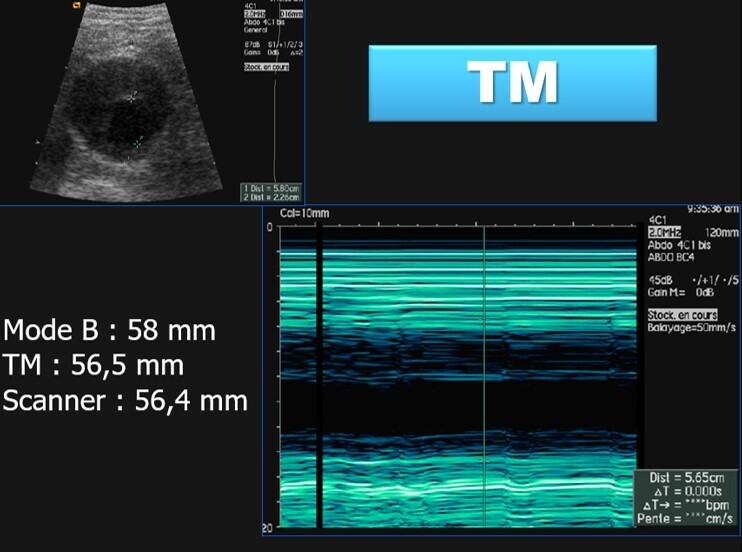

La mesure de diamètre antéro-postérieur (DAP) est le diamètre référence, paroi externe/paroi externe.

Cette mesure doit se faire en mode B et en mode TM, cette dernière est la technique la plus fiable.